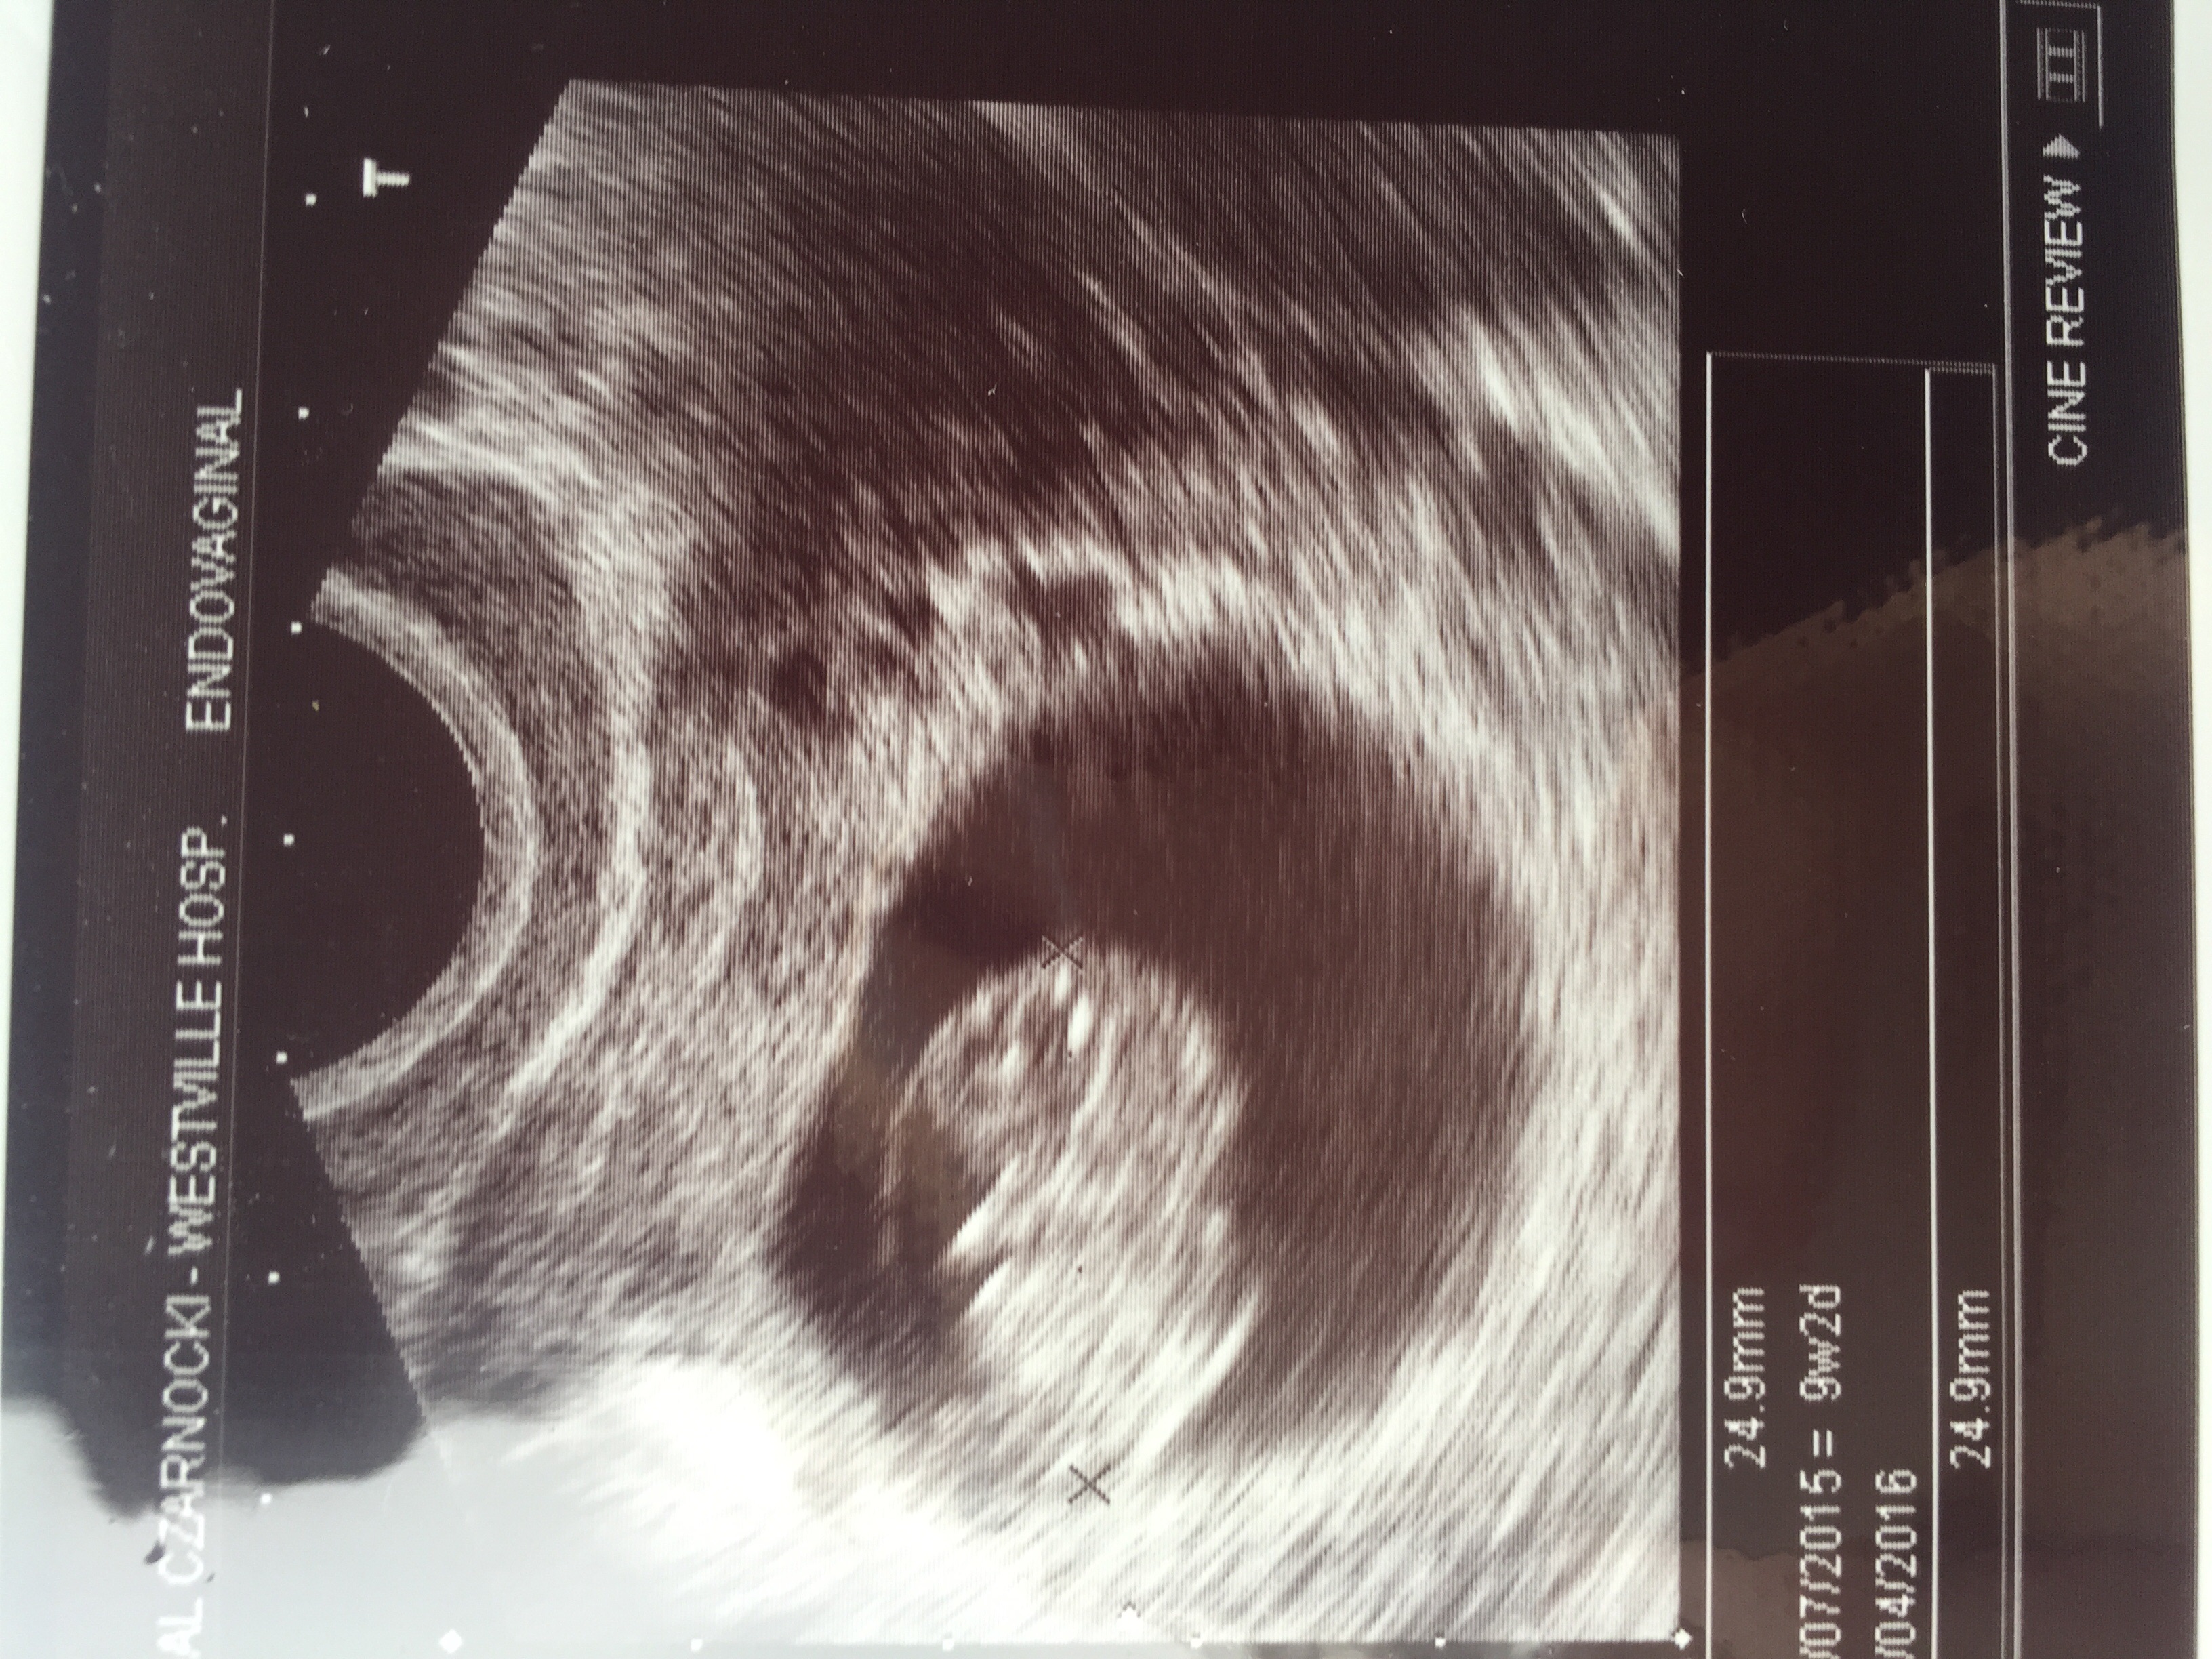

• 9weeks 2days. And I was not prepared for the all the emotions ❤️